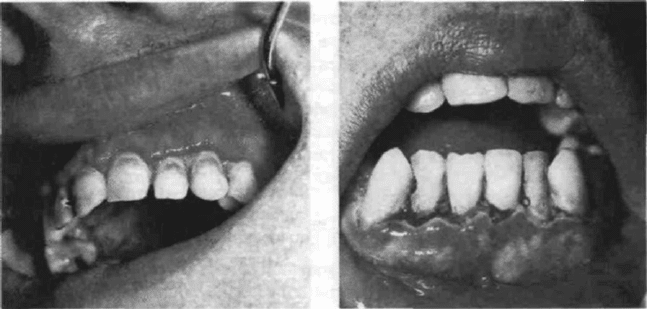

Рис.142. Острый локализованный

язвенный гингивит, легкая степень

вития. Заболеванием может быть поражена десна в области 2-3 зубов — ограни¬

ченный (локализованный) гингивит либо на всем протяжении зубного ряда

челюстей - диффузный (генерализованный) гингивит (рис. 142, 143).